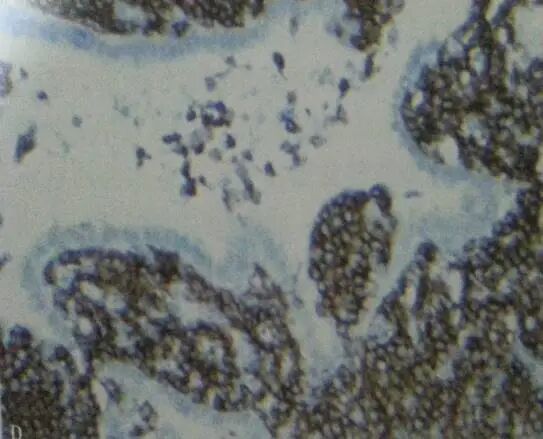

灰白穿刺条,长 0.5 cm,0.7 cm,径 0.1 cm;镜检条索状组织中见淋巴样,细胞弥漫性浸润,细胞小至中等大小,胞质透亮,核形不规则,可见淋巴上皮病变及滤泡植入现象;

免疫组化标记结果:

CD20(+),Pax-5(+),CD3(-),CD5(-),CyclinD1(-),

CD21(部分+),CD23(FDC+),CKpan(上皮+)CD10(-),

CD43 (+),Kappa(部分+),Lambda(-),Ki-67(+,约 7%);

诊断为:(肺) 黏膜相关淋巴组织结外边缘区淋巴瘤 (MALT 淋巴瘤)。

03 病理特征

淋巴细胞浸润及向间质扩张、压迫邻近淋巴滤泡;

粘膜相关淋巴组织的边缘区 B 细胞淋巴瘤;

▶淋巴上皮病变

▶反应性滤泡

▶边缘区细胞或/和单核细胞样 B 细胞

▶小淋巴样细胞

▶浆细胞

▶散在分布的转化母细胞